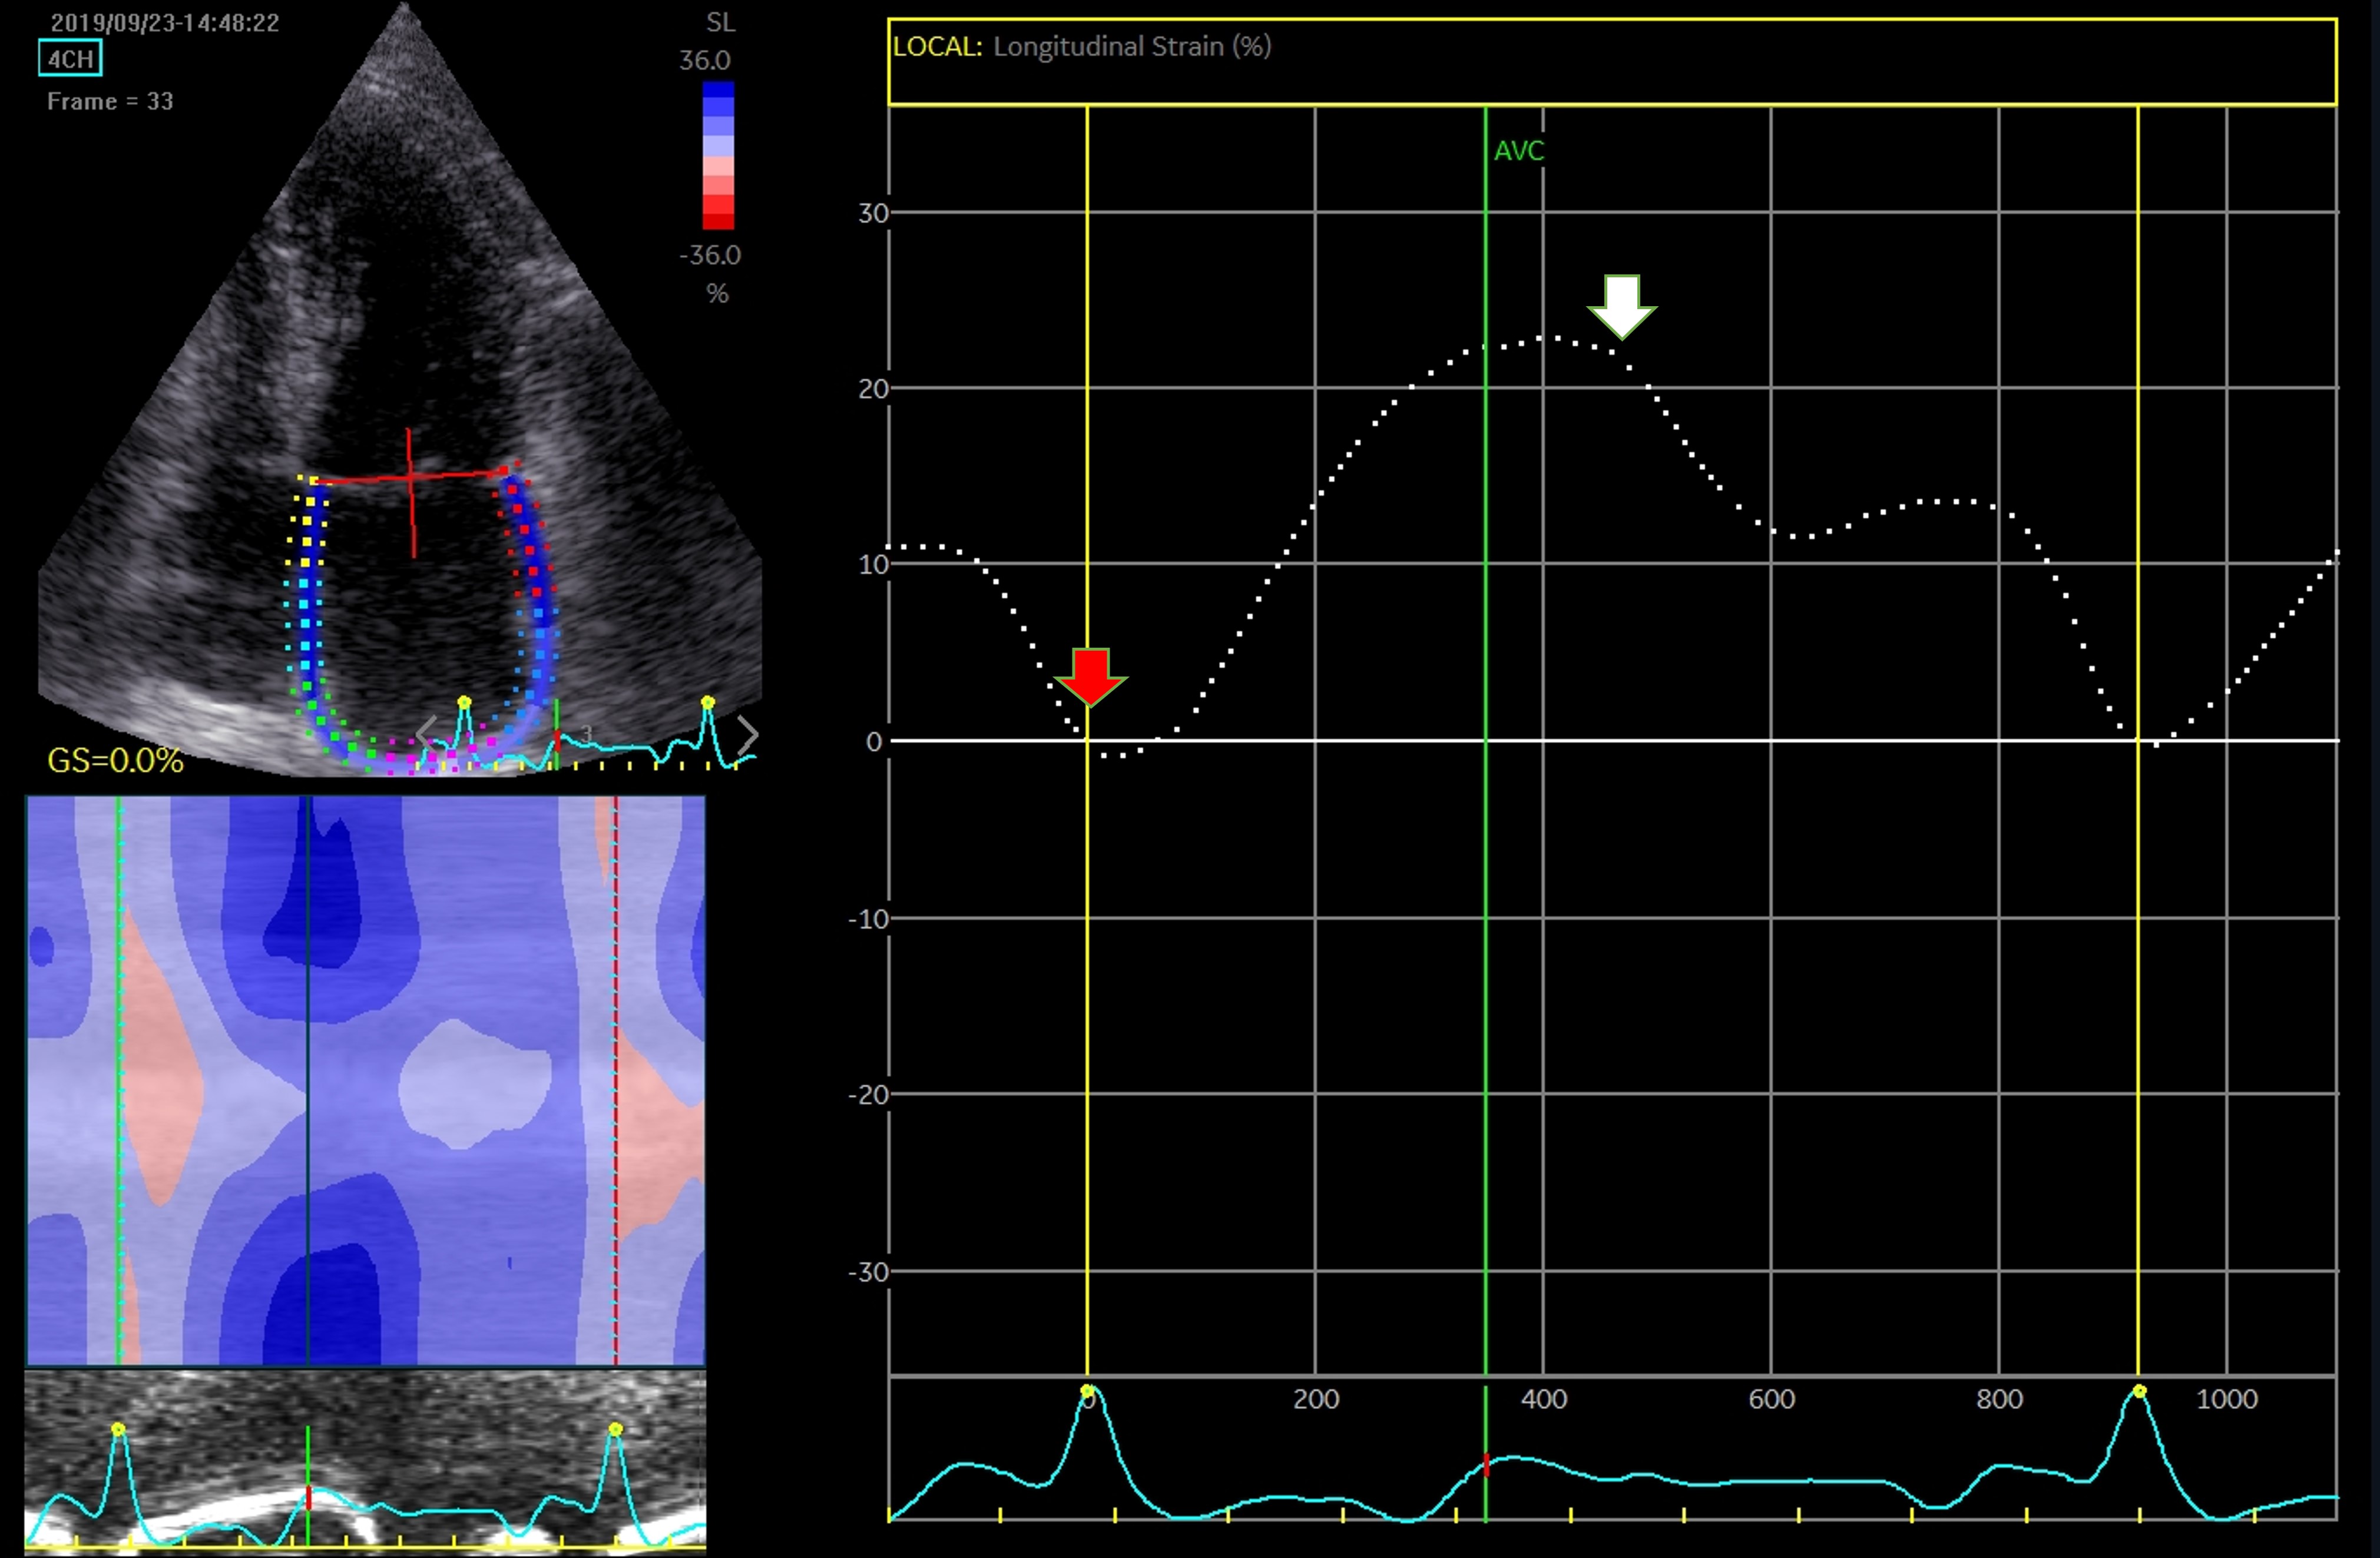

Strain analysis has the advantage of being a semi-automated, angle-independent technique. The need to manually track the LA walls and reposition the region of interest on each segment, makes this investigation time consuming and decreases reproducibility. Until recently, studies relied on a single software, and consensus and interchangeability between different software are still needed. Irrespective of these limitations, atrial strain is validated and correlates with the degree of fibrosis [88]. The assessment can address a 4-chamber view (6 segments) only, or both 4- and 2-chamber views (12 segments), in dedicated optimized views to record a maximized cross-sectional image of the chamber. The recommendations highlight exclusion of pulmonary veins and appendage orifice [53]. Interpretation of LA strain as global strain is advised, while using a single apical 4-chamber view to assess LA longitudinal strain is acceptable. Notably, the interatrial septum is more difficult to visualize. This is the reason why most studies disregarded the interatrial septal deformation and focused on lateral wall movement [89]. The LA septal strain is influenced by its fibromuscular composition and by right atrial pressure. In 2- chamber view, the problem of strain analysis depends on the LA appendage, which often compromises the recognition of speckles and deformation analysis [90]. The measurements may be interpreted using the QRS-complex [53] or the P-wave intervals [91], with similar reproducibility, but better feasibility and shorter time-to-analysis for the former (Figs. 8,9). Moreover, the QRS-complex interval has an advantage when assessing patients with arrhythmias, as AF [92].

Fig. 8.

Fig. 8.Assessment of LA function by speckle tracking echo using the R-R interval – peak systolic LA strain (arrow). Four-chamber view depicting the region of interest (ROI, in the left). The curves represent the mean global LA longitudinal strains. The reference point was set at the onset of the R-wave. The total global strain is positive at the opening of the mitral valve (red arrow). Global strain at atrial contraction is also positive (white arrow). The total global strain is a sum of the negative global strain at atrial contraction (red arrow – at mitral valve closure) and the positive global strain (white arrow – at mitral valve opening).

Fig. 9.

Fig. 9.Strain evaluation of the left atrium using the P-P interval. Four-chamber view depicting the region of interest (ROI, in the left). The curves represent the mean global LA longitudinal strains. The reference point was set at the onset of the P-wave. The total global strain is a sum of the negative global strain at atrial contraction (red arrow – at mitral valve closure) and the positive global strain (white arrow – at mitral valve opening).